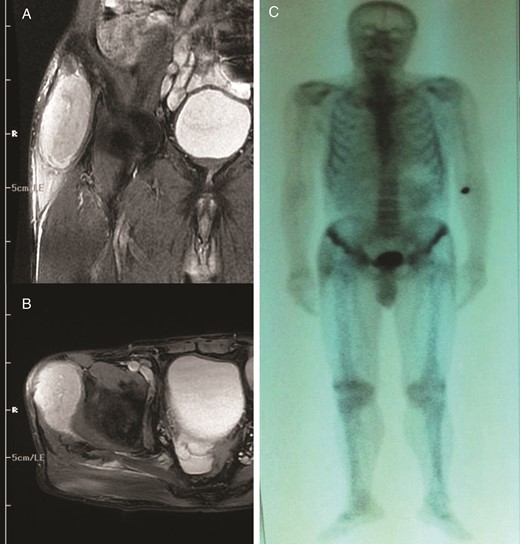

A 74-year-old man presented to the orthopedics outpatient clinic with painless swelling on his right leg that had developed progressively in the last 3 months. He underwent right radical nephrectomy for RCC 7 months prior. A pathological examination of the right kidney demonstrated the presence of clear cell carcinoma and Fuhrman grade IV (pT2 N0 Mx). On physical examination, an 8 × 6 cm hard mass was palpable on the lateral aspect of his right leg. MRI of his right leg revealed a 10 × 8.5 × 5.5 cm tumor located in the gluteus medius muscle (Fig. 3A and B). Computed tomography, ultrasonography and MRI did not reveal any liver or retroperitoneal lymph node metastasis. A total body bone scan of the patient showed no abnormalities (Fig. 3C). Biopsy of the muscle mass documented an RCC metastasis (Fig. 4A and B). The mass was completely removed from the right leg. The patient underwent three cycles of immunotherapy regimen, including IFN-α.

Coronal (A) and axial (B) T2-weighted axial magnetic resonance image of the right gluteus medius muscle showing avid enhancement of the soft tissue component. (C) Total body bone scan image.